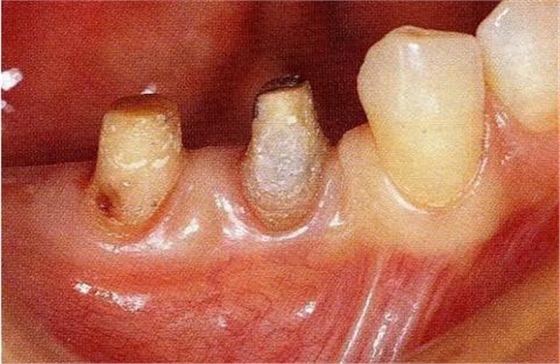

圖18-4▲正畸結(jié)束后6個(gè)月,骨外科處理后的狀態(tài)。附著齦嚴(yán)重不足。

圖18-5▲骨外科處理后牙槽骨平坦,同時(shí)為了獲取附著齦進(jìn)行游離齦瓣移植。